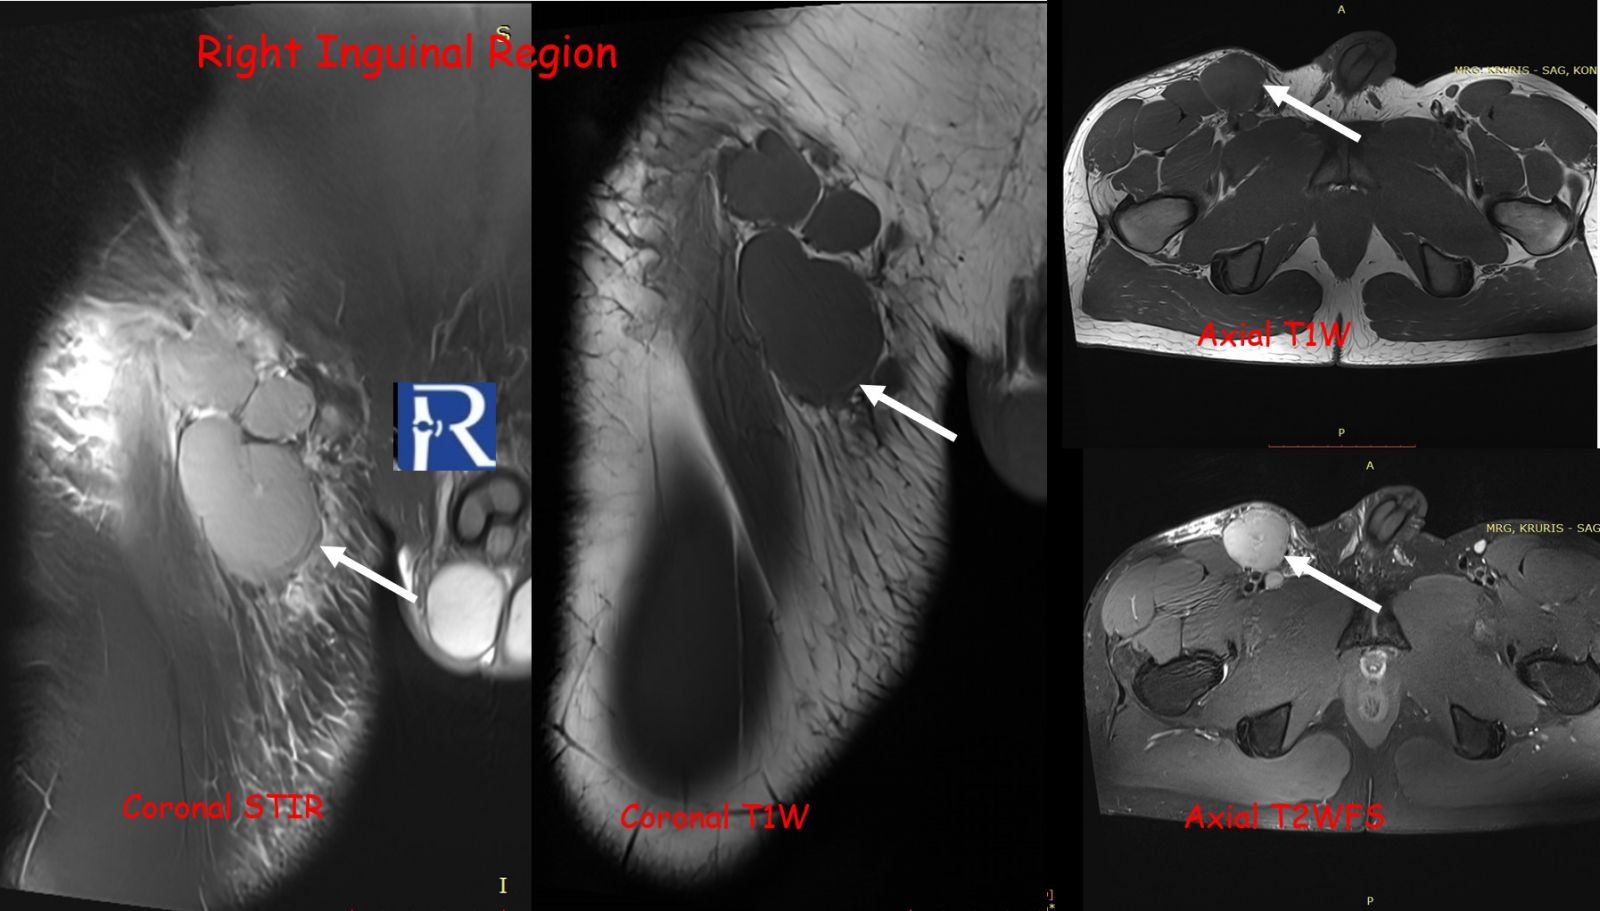

The lesion exhibited limited cortical destruction, yet extensive soft-tissue extension. Multiple conglomerate inguinal and pelvic lymph node enlargements were also identified, demonstrating signal characteristics similar to those of the primary lesion.

These imaging findings—particularly the absence of periosteal reaction, intermediate T2 signal, and marked DWI restriction—favored the diagnosis of lymphoma over Ewing sarcoma.

However, certain imaging clues may guide the differential diagnosis. Lymphoma typically demonstrates limited cortical destruction, absence of periosteal reaction, and intermediate T2 signal intensity, whereas Ewing sarcoma tends to produce more prominent periosteal layering and higher T2 hyperintensity. Diffusion-weighted imaging is a powerful adjunct, with strong restriction patterns highly suggestive of lymphoma due to its dense cellular structure.

This case illustrates how radiologic–pathologic correlation is vital for differentiating PBL from small round blue cell tumors, such as Ewing sarcoma. Accurate diagnosis impacts management, as PBL responds well to combined immunochemotherapy (e.g., R-CHOP regimen) and radiation, whereas Ewing sarcoma typically requires surgical resection with adjuvant chemotherapy.